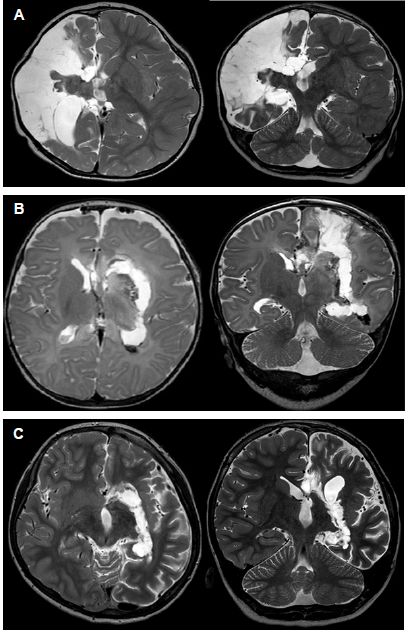

功能性大脑半球切开术的目标是完全隔离病理性半球,控制癫痫发作而且并发症最小。手术的4个要求:离断皮质丘脑束,离断内囊和放射冠传导纤维;切除颞内侧结构;胼胝体全切开;离断眶-额-下丘脑束,切断额叶水平纤维。功能性脑半球切开术的主要入路:经外侧裂岛叶周围入路(图1A)以及胼胝体和侧脑室的垂直入路(图1B、1C)。

图1. 功能性大脑半球切开术的术后MRI成像。A.岛周功能性半球切开术;B.经皮质、脑室功能性半球切开术;C.经胼胝体、脑室功能性半球切开术。

岛周入路切开术有3个手术步骤:切开上环岛沟(上岛窗)、下环岛沟(下岛窗)和切除岛叶皮质。经上岛窗到达胼胝体,进入侧脑室分离额、顶叶皮质与放射冠白质,包括皮质丘脑束,注意保留动脉和静脉。沿胼周动脉切开胼胝体后,再通过上岛窗在脉络裂至穹隆伞水平向后至海马尾部及向前至基底核前部,离断额叶底部。经下岛窗,在颞上回水平行颞叶切除术,包括钩突、杏仁核和海马。岛叶皮质通过软膜下抽吸或在屏状核水平切开。

矢状窦旁入路切开术是通过额后皮质窗(图1B)或胼胝体(图1C),操作与岛周入路切开术相同。经典的胼胝体切开术通过小骨窗到达侧脑室,经内囊外侧至丘脑部、侧脑室三角区和颞角,进行额、顶皮质和放射冠切开,然后行颞叶切除术。